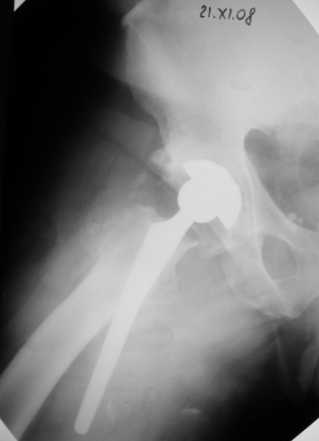

Глеб Коробушкин 05 Декабрь 2008, 00:15

Сегодня свершилась ревизия. С максимально бережным отношением к тканям выделил бедро.

Ножка "слету " удалить не удалось, после выделения долотом ножку удалил.

Поставил Corail большего размера.

Рентгенограммы вывешу.